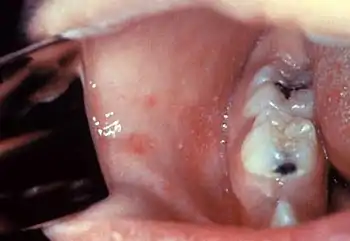

Koplik's spots seen inside the mouth are diagnostic for measles, but are temporary and therefore rarely seen.[28] Koplik spots are small white spots that are commonly seen on the inside of the cheeks opposite the molars.[27] They appear as "grains of salt on a reddish background."[30] Recognizing these spots before a person reaches their maximum infectiousness can help reduce the spread of the disease.[31]

A Filipino baby with measles Koplik's spots on the third pre-eruptive day

Koplik's spots on the third pre-eruptive day Koplik's spots on the day of measles rash

Koplik's spots on the day of measles rash

Typically, clinical diagnosis begins with the onset of fever and malaise about 10 days after exposure to the measles virus, followed by the emergence of cough, coryza, and conjunctivitis that worsen in severity over 4 days of appearing.[60] Observation of Koplik's spots is also diagnostic.[31] Other possible condition that can result in these symptoms include parvovirus, dengue fever, Kawasaki disease, and scarlet fever.[61] Laboratory confirmation is, however, strongly recommended.[62]